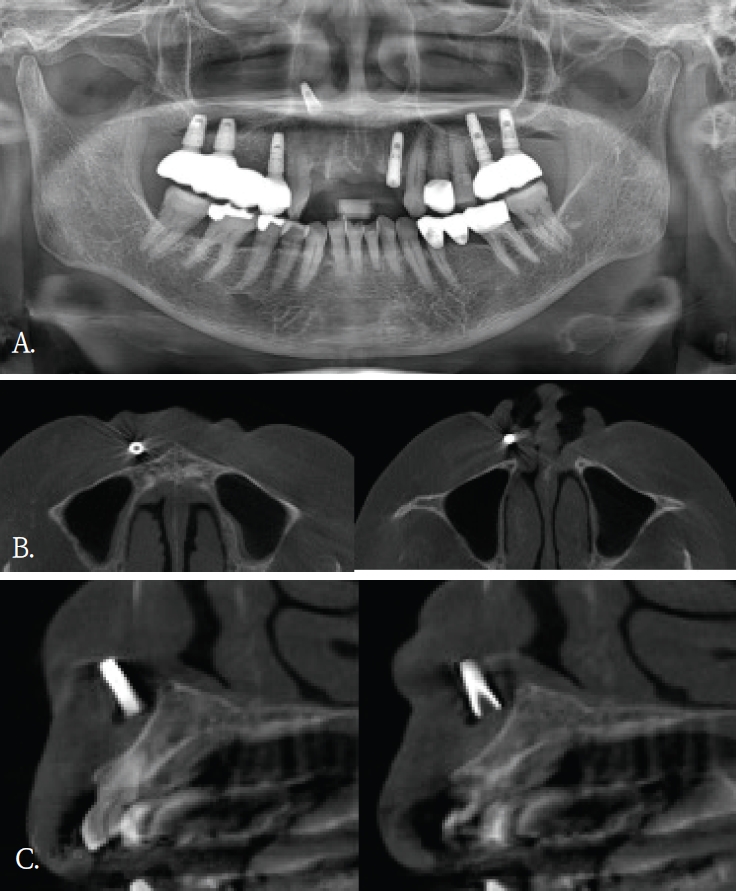

Fig. 1.

A. Panoramic radiograph shows no definite abnormality in the maxillary anterior region. B. Cross-sectional cone-beam computed tomographic image of the maxillary anterior alveolar region demonstrates a small block-shaped radiopaque foreign body in the labial soft tissue, without intraosseous involvement.

20대 여자환자가 윗 입술의 불편감을 주소로 내원하였다. 파노라마방사선영상에서 관련된 이상소견이나 병변이 관찰되지 않았다(Fig. 1A). 과거병력 청취에서 교통사고로 인한 윗 입술 열상의 봉합 병력이 있었음을 파악한 후, 외상 후 연조직 섬유화로 진단되었다. 1년 후, 이물감을 호소하면서 환자는 재내원하였다. 파노라마방사선영상에서는 여전히 이상소견이 관찰되지 않았기에, 콘빔CT검사를 시행하였다. 윗입술과 상악 전치사이 연조직부위에서 블럭모양의 방사선불투과성 이물질이 발견되었다(Fig. 1B). 이물질 제거를 위한 외과적 수술이 시행되었고, 술 후 해당 이물질은 유리조각임이 확인되었다.

증례 1에서도 초진시 파노라마영상에서는 유리조각을 관찰할 수 없었기에 연조직 병변으로 진단되었으나, 재내원후 촬영된 콘빔CT영상에서 연조직내에 있었던 이물질임으로 확인된 경우이다. 윗입술에 있었던 유리조각이 방사선불투과성 물질이였지만, 상악 전치부와 중첩되어 파노라마방사선영상에서 뚜렷하게 구분되지 않았다.